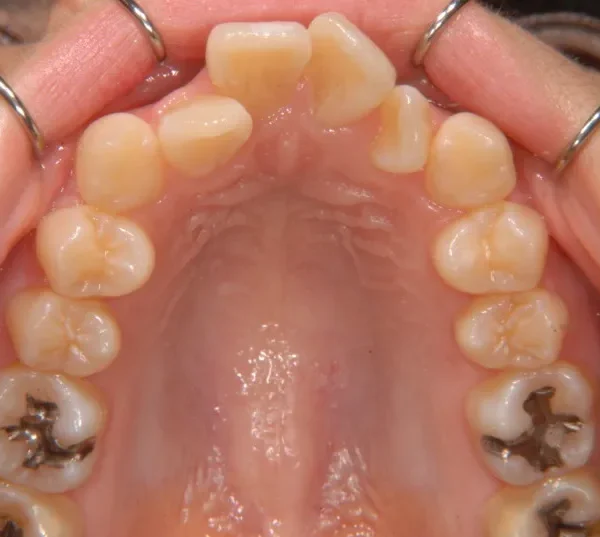

初診時年齢 19~29歳 (女性) 主訴 ガタガタ・90度ねじれている

診断名 叢生・上顎前突 装置名

奥歯が内側と前方にかたむき上下の歯がガタガタに生えています。

90度ねじれた歯もあります。前歯も出っ歯になっています。

歯は抜かず、歯科矯正用アンカースクリューを用いて治療しました。

治療回数○回、2年9ヶ月の治療期間で矯正治療を終了しました。

主訴が改善され、ご満足頂きました。